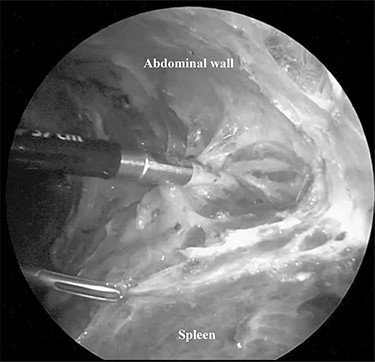

The patient was placed in the right lateral decubitus position. The standing positions of the surgeon and the assistant were on the right or left of the patient depending on the surgical site. Initially, a 12-mm port was introduced through the lateral margin of the left rectus abdominis muscle at the level of the umbilicus. After establishment of pneumoperitoneum with an intra-abdominal pressure of 10 mmHg, two 3-mm ports were inserted in the left upper quadrant at the subxiphoid and left subcostal margin along the mid-axillary line. The accessory spleen was carefully explored through the abdomen. The spleen was mobilized from the lower to upper direction. The initial dissection involved release of the lower pole of the spleen with dissection of the splenocolic ligament, and the spleen was freed from the splenorenal ligament toward the posterior aspect of the splenic hilus using laparoscopic coagulating shears under the guidance of a 3.3-mm needlescope (Karl Storz SE & Co. KG) (Fig. 2). Subsequently, short gastric vessels (Fig. 3) were divided, and the upper pole of the spleen was mobilized with the division of the splenophrenic ligament. Then, the splenic hilus was divided using a linear stapler (Fig. 4). The isolated spleen was then placed in an impermeable bag (Endo-Catch II; Covidien Co. Ltd.) and extracted via a 12-mm port after morcellation using the placenta forceps without extending the initial 12-mm incision (Fig. 5). After irrigation with normal saline and confirmation of hemostasis around the resected area without inserting a suction drain, only the 12-mm port site was only closed, and the 3-mm port sites were left open.

The splenic hilum was divided using an Endo-GIA linear stapler.